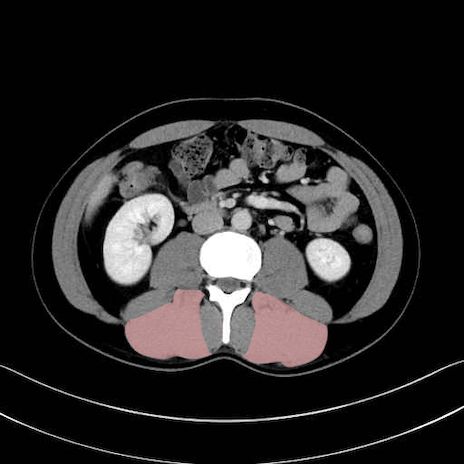

脊柱起立筋(erector spinae)のCT画像の解剖

脊柱起立筋 (Erector spinae)

多裂筋 (Multifidus)